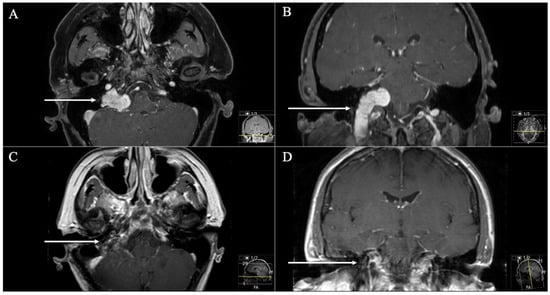

3. Results

3.1. Patient Population

3.2. Postoperative Outcome